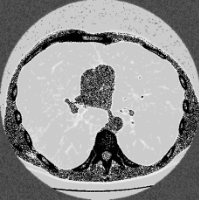

Table 3. Enhancement using dehazing and estimation of illumination for lung images of different datasets

Input Image

Output 1

Output 2

Final Enhanced Image

Lungs-1

Lungs-2

Lungs-3

Lungs-4

Note: This table is showing some lung images intermediate and final enhanced forms.

In Table 3, different dataset lung images' intermediate and final enhanced forms are showing. In the Table 4. we are showing the comparison between the calculated discrete entropy of enhanced images, PSNR, GMSD, and MCSD score for our proposed method as well as for Adaptive Gamma Correction with Weighting Distribution Method (AGCWD). In our proposed enhancement method, Entropy and GMSD score is always better than AGCWD method. High entropy is often desirable for images with complex textures and a lower value of GMSD indicates the improved quality of an image.